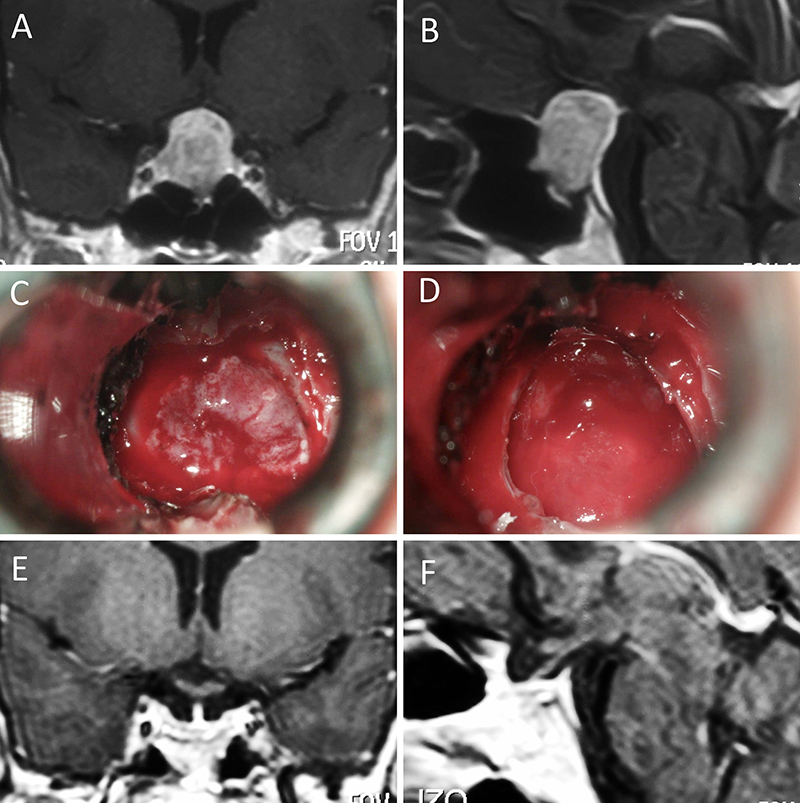

Figura 7: Acromegalia en mujer de 39 años. Con remisión bioquímica tras la cirugía. A-B: RM preoperatoria; C-D: intraoperatorio; E-F: RM postoperatoria.

Figura 8: Acromegalia en mujer de 50 años. Con remisión bioquímica tras la cirugía. A-B: RM preoperatoria; C-D: intraoperatorio; E-F: RM postoperatoria.

Figura 9: Acromegalia en mujer de 54 años. Con remisión bioquímica tras la cirugía. A-B: RM preoperatoria; C-D: intraoperatorio; E-F: RM postoperatoria.

Figura 10: Acromegalia en mujer de 54 años. Se objetivo previo a la cirugía un componente significativo del tumor invadiendo el seno cavernoso derecho. No se logró remisión bioquímica tras la cirugía. A-B: RM preoperatoria; C-D: intraoperatorio; E-F: RM postoperatoria.

Acromegalia

En la literatura mundial las tasas de remisión bioquímica global en acromegalia van del 42 al 83%.4,11,28,30,32,33,37,39,42,50,52,53,56,58 Nosotros obtuvimos una tasa de remisión global del 75%, valor que se encuentra dentro del rango obtenido por centros internacionales especializados.

Nomikos et al. encontró una correlación significativa entre tamaño del adenoma y tasa de remisión: 75,3% en microadenomas, 48,6% en macroadenomas y 8,3% en gigantes.49 Jane et al, en un estudio multicéntrico, describe una tasa de remisión del 100% para microadenomas, 61% para macroadenoma y 45,5% para los mayores a 2 cm.37 En nuestra serie se logró la remisión en 95% de los microadenomas y 61% de los macroadenomas, lo que se asemeja a esto último.

Finalmente, cabe destacar que diversos estudios mutivariados6,47,59 concluyen en que la invasión del seno cavernoso es un predictor de no-remisión. En este sentido, el equipo de Erlagen demostró que las tasas de remisión que obtuvieron del 72,2% en adenomas no-invasivos, cayeron a un 21,6% en los invasores.49 En nuestra serie, en la totalidad de pacientes acromegálicos sin remisión (25%, n=13) se evidenció un Knosp alto.